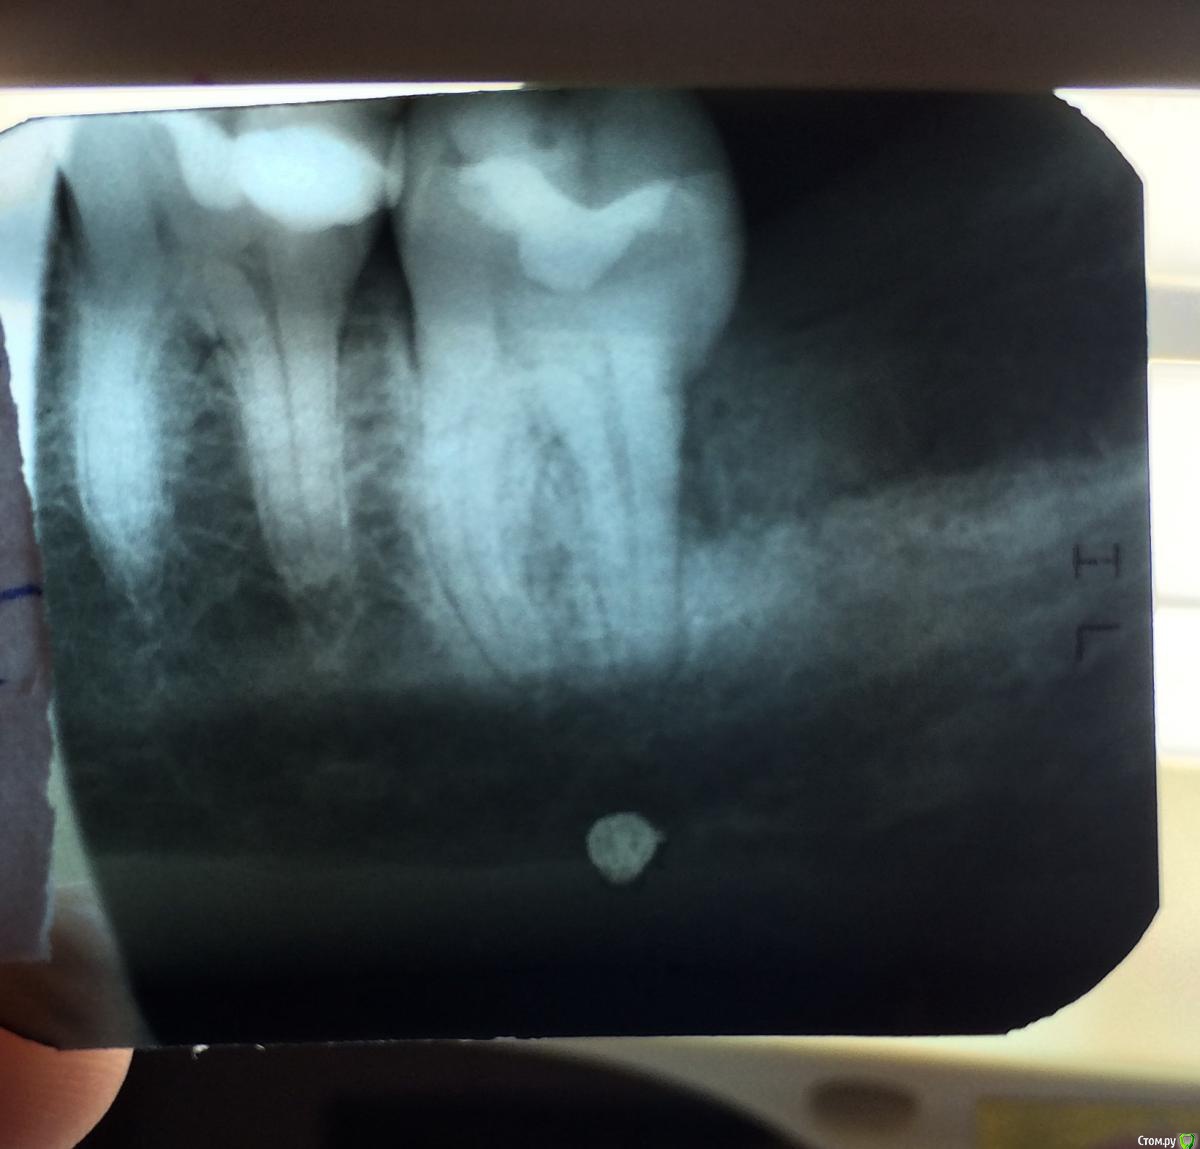

Irina2408 Опубликовано 8 марта, 2016 Поделиться Опубликовано 8 марта, 2016 Полечила ещё один зубик и опять проблемы. На этот раз обошлось без депульпирования. Был глубокий кариес. Сегодня 4 день после лечения, зуб продолжает ныть, особенно ночью, реагирует на холодное и горячее. Почему так? Ошибка доктора? Замечу, что до лечения не беспокоил вообще . Зуб 37. Ссылка на комментарий

ЕленаВалерьевна Опубликовано 8 марта, 2016 Поделиться Опубликовано 8 марта, 2016 у Вас в теме от 4 марта точно такой же снимок, но Вы там про периодонтит 36 уточняете. так здесь то снимок новый? после лечения кариеса 37 зуба? или всё же до лечения?на холодное горячее ноет точно 37 пролеченный? Ссылка на комментарий

Irina2408 Опубликовано 8 марта, 2016 Автор Поделиться Опубликовано 8 марта, 2016 Снимок старый. После лечения снимка нет. На холодное , горячее точно 37, а что ноет не всегда понятно, иногда кажется, что вообще вся левая сторона. По крайней мере, началось все это после лечения этого 37((( Ссылка на комментарий